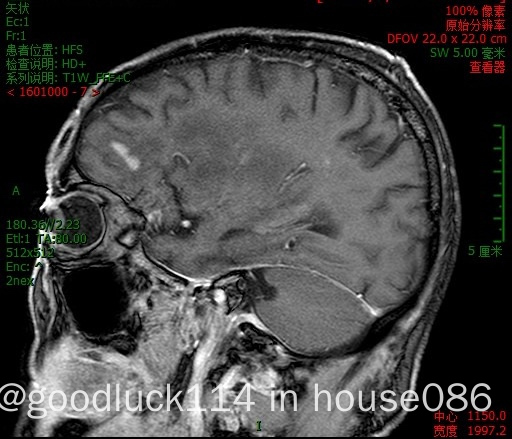

高龄取不了病理,医院做不了pet-ct,做了头颅ct和mri,发现颅内占位性病变,怀疑原发或转移,但胸部ct腹部ct和肿瘤标志物都没有明显异常,也没有除神经系统外其他系统的症状,mri增强结果不像是胶质瘤,高度怀疑是原发性中枢淋巴瘤。